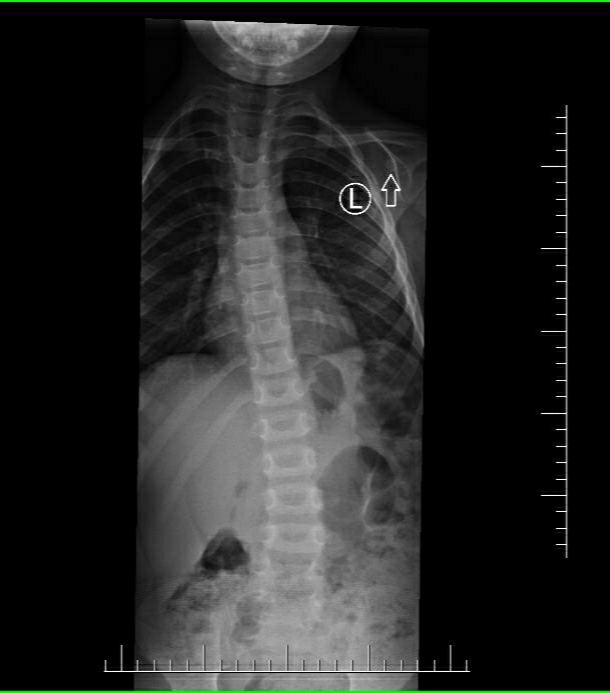

Maciuś zmaga się z poważną wadą kręgosłupa, obniżonym napięciem mięśniowym, wadą wzroku i kilkoma innymi problemami. Zbiera na codzienną rehabilitację, basen i zajęcia ruchowe oraz sprzęty ułatwiające mu prawidłowe funkcjonowanie. Dzielnie walczy, żeby Jego życie w przyszłości wyglądało normalnie.